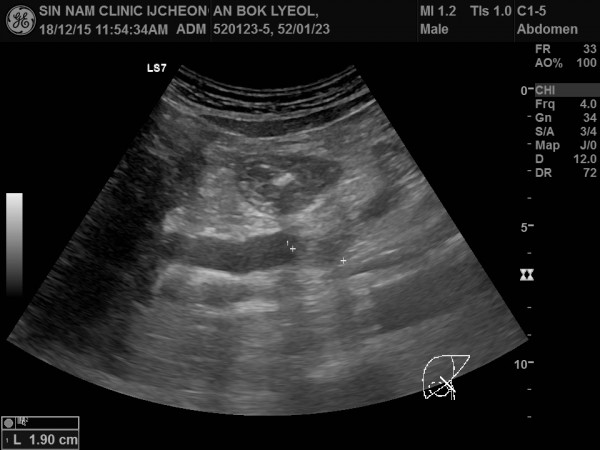

담관암, 담도암, 상복부 초음파